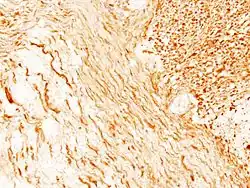

Guz zbudowany jest z jednorodnych komórek o morfologii komórek Schwanna. Jądra komórkowe są wydłużone, układają się w wiry, pasma lub palisady. Charakterystyczne dla guza jest tworzenie tzw. ciałek Verocaya. W części przypadków wraz ze wzrostem gęstości komórkowej jądra przyjmują okrągły lub wieloboczny kształt. Typ histologiczny w którym komórki są zbite i ustawione palisadowato określa się jako Antoni A; typ w którym komórki są ułożone nieregularnie i luźno to typ Antoni B.